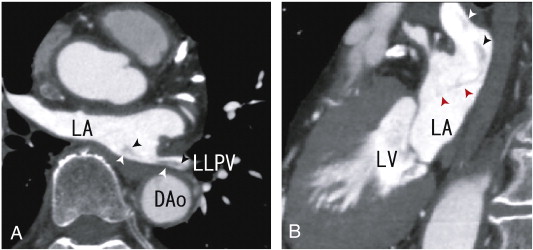

The patient was treated with 100 mg of aspirin without warfarin. The EKG indicated normal sinus rhythm, a normal axis and no ST-T changes, and the patients heart rate was 59 beats/min. A 64-MDCT scan was performed to assess the stenosis of the coronary artery because of recent chest pain. Although the stenosis of the coronary artery was not diagnosed, a large thrombus in LLPV and in LA was noninvasively identified as a defect in enhancements by 64-MDCT scan, which was shown in my previous paper [4]. A pulmonary vein thrombus was identified in LLPV as a defect in contrast enhancements (Fig. 1A and B). The thrombus was visualised using transthoracic echocardiography (TTE) in Fig. 2. In video images using TTE, a thrombus in the LA was demonstrated to be a large bright echodensity, suggesting a thrombus with a highly fibrinous component. The shape of the thrombus in video images was a wavelike, which indicated that the thrombus exhibited flexibility and was rather strong. Some parts of the thrombus attached to the mitral valve were not identified by a 64-MDCT. The volume of the LA was 39 ml, and the patient exhibited no thrombi in the LAA. In this case, TEE can assess the quality and quantity of a left atrial thrombus, but it cannot identify a pulmonary vein thrombus, which is well assessed by a 64-MDCT scan.

A. 64-MDCT axial images demonstrating a thrombus from the left lower pulmonary ...

Fig. 1.

A. 64-MDCT axial images demonstrating a thrombus from the left lower pulmonary vein to the left atrium (LA) (arrowheads) as the defect of enhancement. The middle parts of the thrombus were illustrated weakly. DAo; descending aorta, LA; left atrium, LLPV; left lower pulmonary vein.

B. 64-MDCT sagittal images demonstrating the thrombus from the left lower pulmonary vein to the left atrium (LA) (arrowheads). The merge of the thrombus was vague. A vague, thin line-like defect was observed (red arrowheads). This thin line may represent a thrombus connecting mitral valve. A part of the thrombi seemed to be attached to the posterior wall of LA. DAo; descending aorta, LA; left atrium.